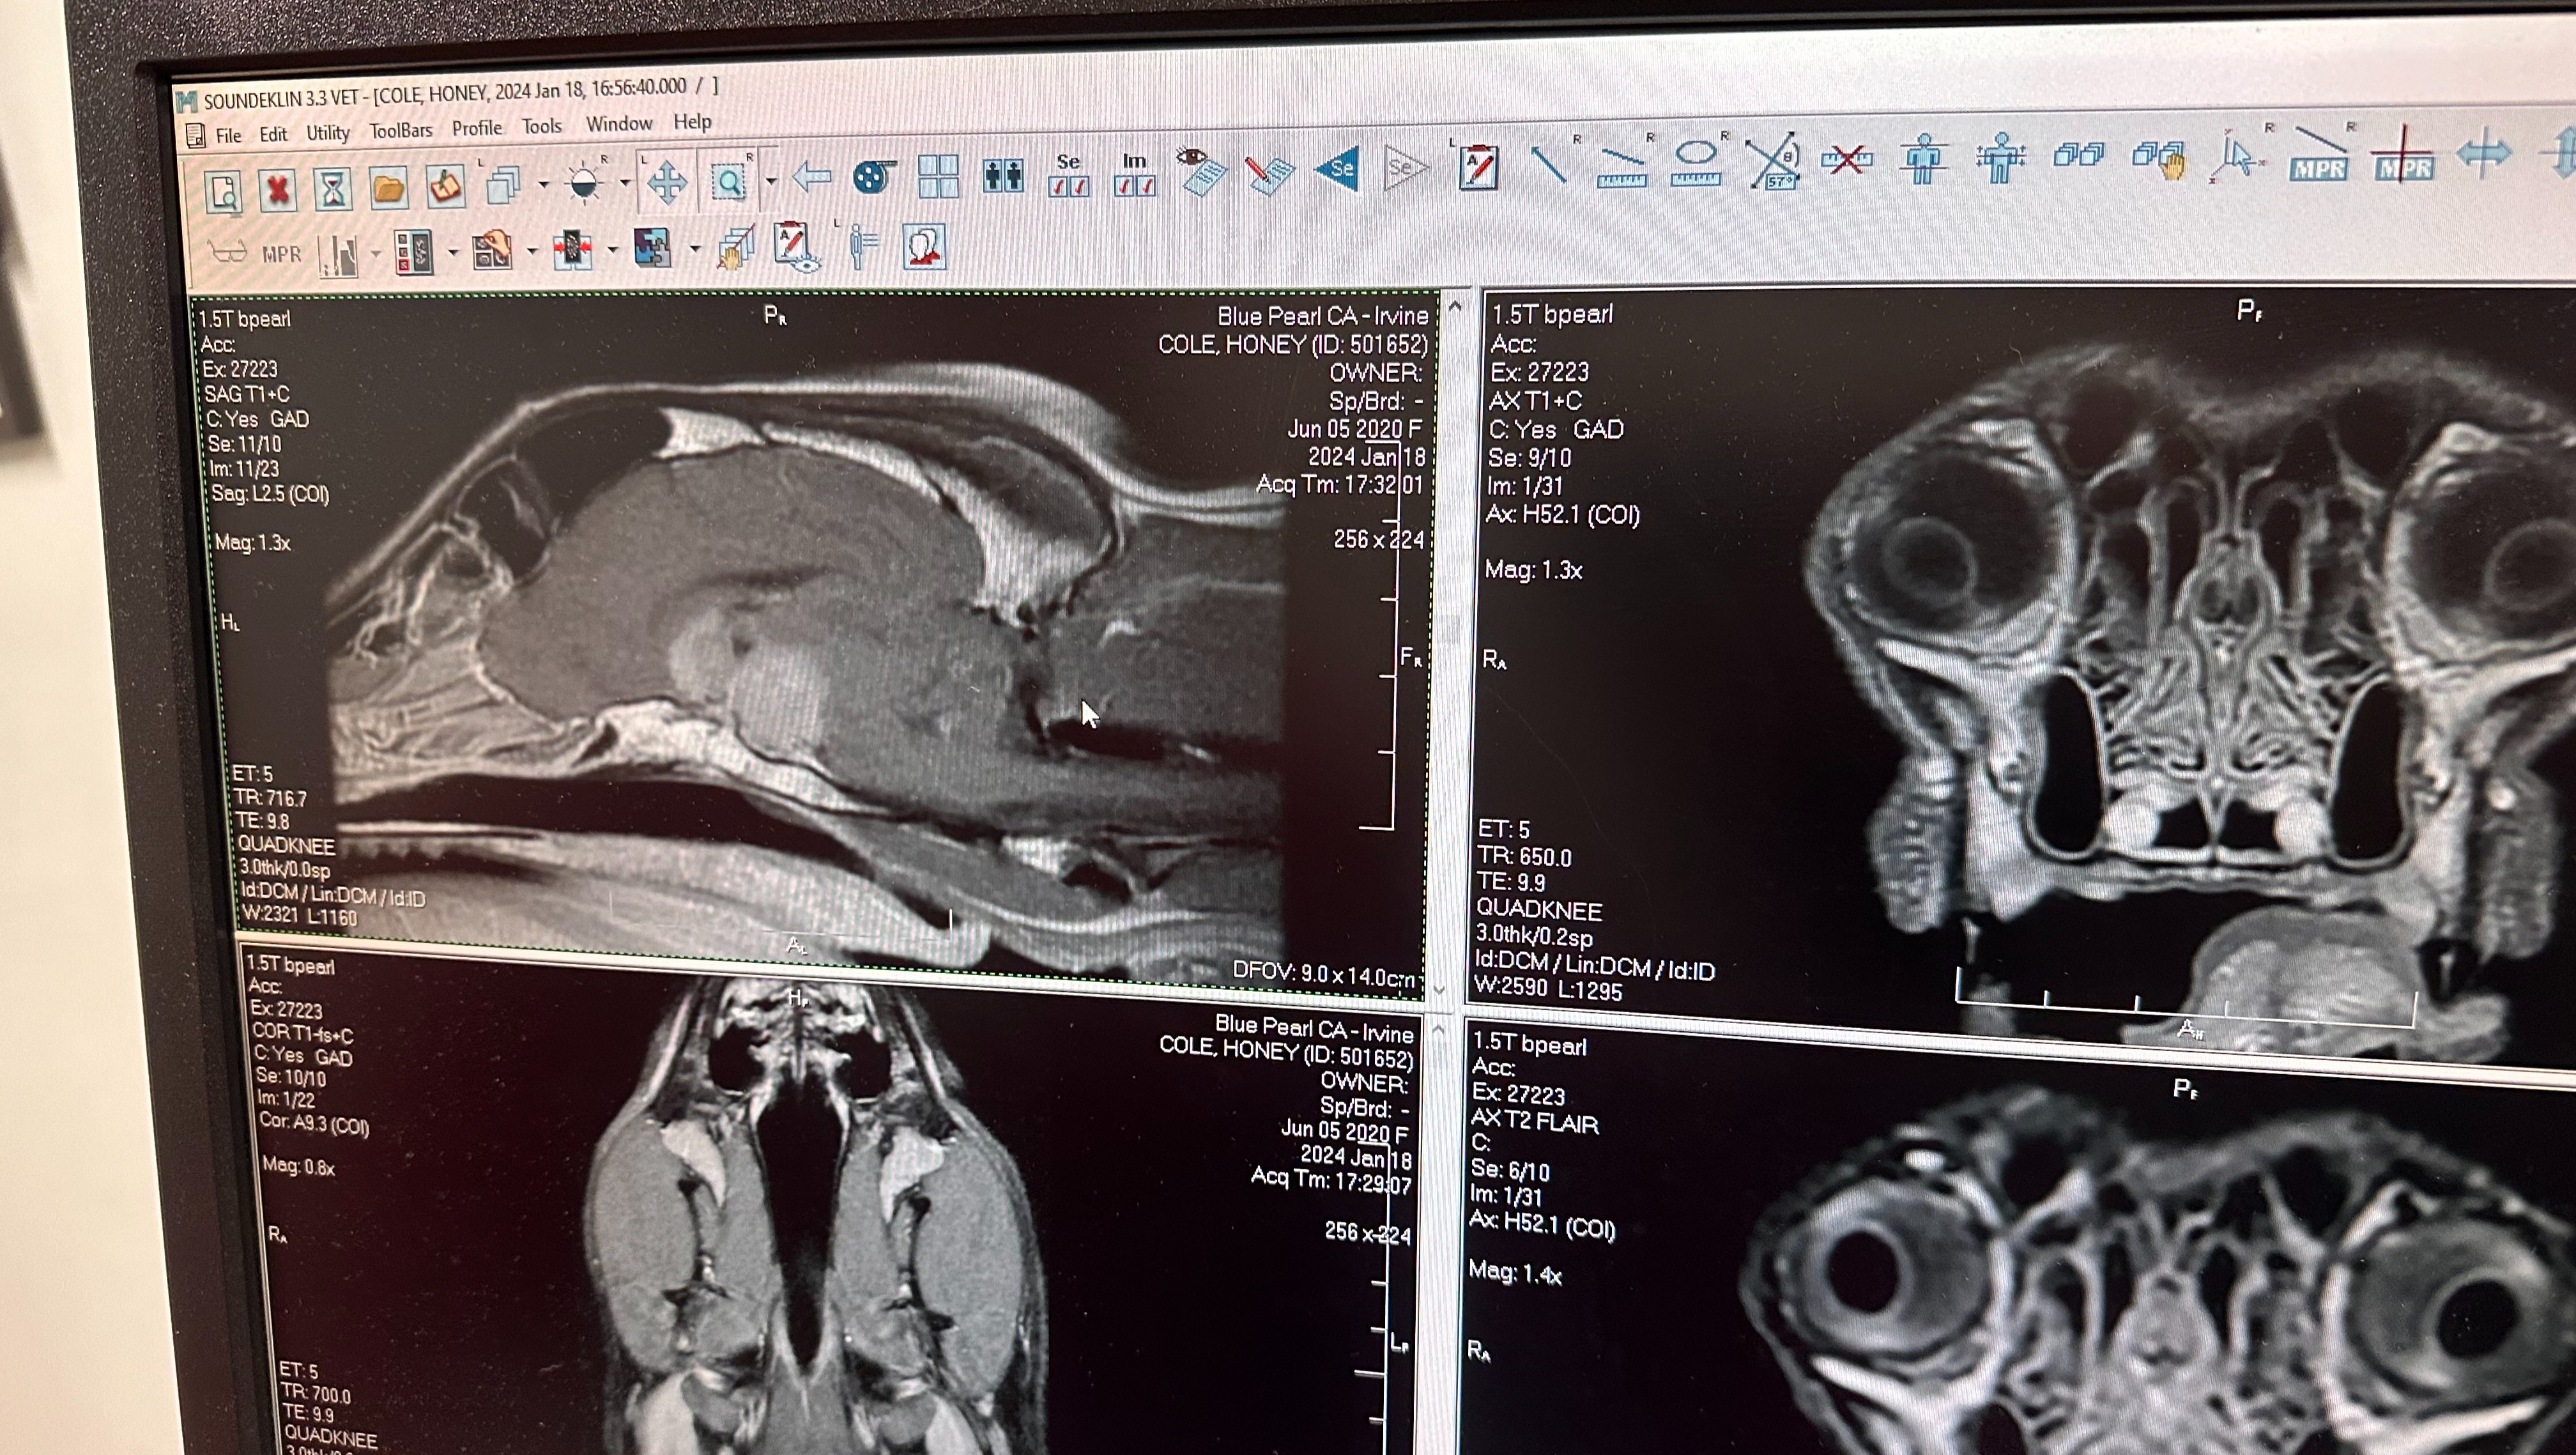

Hello my name is Kaylan Cole and after much contemplation, we've decided to reach out through this GoFundMe in the hope of receiving assistance as we face the overwhelming challenge of our beloved Honey's recent diagnosis. On January 18th, our three-year-old Border Collie Mix, Honey, was diagnosed with an incredibly rare pituitary macroadenoma tumor, leaving us with no option for a cure other than radiation.

This devastating news came upon us swiftly, and Honey, who is not just a pet but a cherished member of our family, has become the center of our concern. Desperate to ensure she has the chance for more healthy years, we're exploring every avenue possible, starting with radiation. The uniqueness of her case has left doctors astonished – they've never encountered a tumor of this size in a dog so young.

Attached are some photos of her as well as her MRI scan with the tumor.